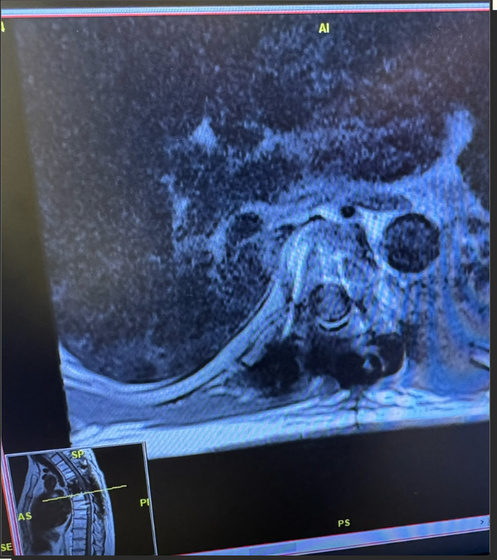

しかし、新規公開株式(IPO)を行った翌年の2022年、ラブランディ氏は胸に痛みを感じて救急外来を受診し、骨肉腫、いわゆる骨のガンを患っていたことが発覚。6cmの腫瘍が神経を圧迫し、脊椎にまで浸潤していたため、椎骨を取り除き、脊椎をチタンのフレームで固定したそうです。

シブランディ氏自身はシングルセル解析により、腫瘍に線維芽細胞マーカーが強く出ていることを確認し、2025年2月にドイツでFAP放射性リガンド療法を受けました。この決断は、腫瘍が脊椎にあり手術が極めて困難だった状況を打破するためでした。治療の結果、3月には腫瘍が劇的に縮小して4月には切除手術が可能となり、6月のスキャンでは腫瘍が検出されない状態にまで回復したとのこと。この過程で、腫瘍内のT細胞浸潤率が20.0%未満から80.0%以上に増加するという劇的な免疫環境の変化も確認されています。